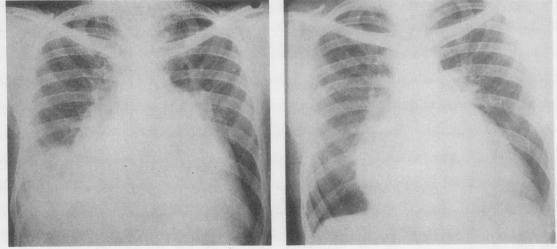

The first 16 patients to have mitral valve replacement with the Starr-Edwards prosthesis at St. Bartholomew's Hospital, London, were reviewed from one to three years after operation. These patients had presented with serious mitral valve disease and there was a high incidence of severe dyspnoea and persistent congestive failure before operation. There were four operative deaths, and two survivors had poor results due to regurgitation alongside the prosthesis. The remaining 10 patients showed considerable improvement. Although no diuretics were given after operation there was little dyspnoea and congestive failure resolved. Anticoagulant therapy is given after operation, and there have been few embolic incidents. The pulmonary vascular resistance was raised to between 6 and 11 units before operation in six patients. There was no undue mortality in this group, and post-operative cardiac catheterization showed a considerable fall in resistance and an increase in cardiac output, suggesting resolution of the pulmonary vascular obstruction. Tricuspid incompetence in these patients disappeared post-operatively. We conclude that mitral valve replacement can restore a patient severely disabled by mitral valve disease to a nearly normal life. We do not regard pulmonary hypertension as a contraindication to operation.

对伦敦圣巴塞洛缪医院首批16例使用斯塔尔-爱德华兹人工瓣膜进行二尖瓣置换术的患者进行了术后1至3年的随访。这些患者均患有严重的二尖瓣疾病,术前重度呼吸困难和持续性充血性心力衰竭的发生率很高。手术死亡4例,2例幸存者因人工瓣膜旁反流效果不佳。其余10例患者有明显改善。术后未使用利尿剂,呼吸困难轻微,充血性心力衰竭得到缓解。术后给予抗凝治疗,栓塞事件很少。6例患者术前肺血管阻力升至6至11单位。该组患者无过高死亡率,术后心导管检查显示阻力显著下降,心输出量增加,提示肺血管阻塞得到缓解。这些患者的三尖瓣关闭不全术后消失。我们得出结论,二尖瓣置换术可使因二尖瓣疾病严重致残的患者恢复到接近正常的生活。我们不认为肺动脉高压是手术的禁忌症。